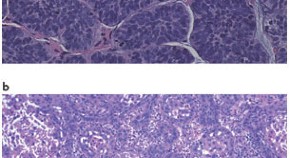

• Hodgkin's lymphoma is a unique B-cell malignancy. This Review discusses the aetiology and genetics of this disease and its distinguishing features.

• Ralf Küppers